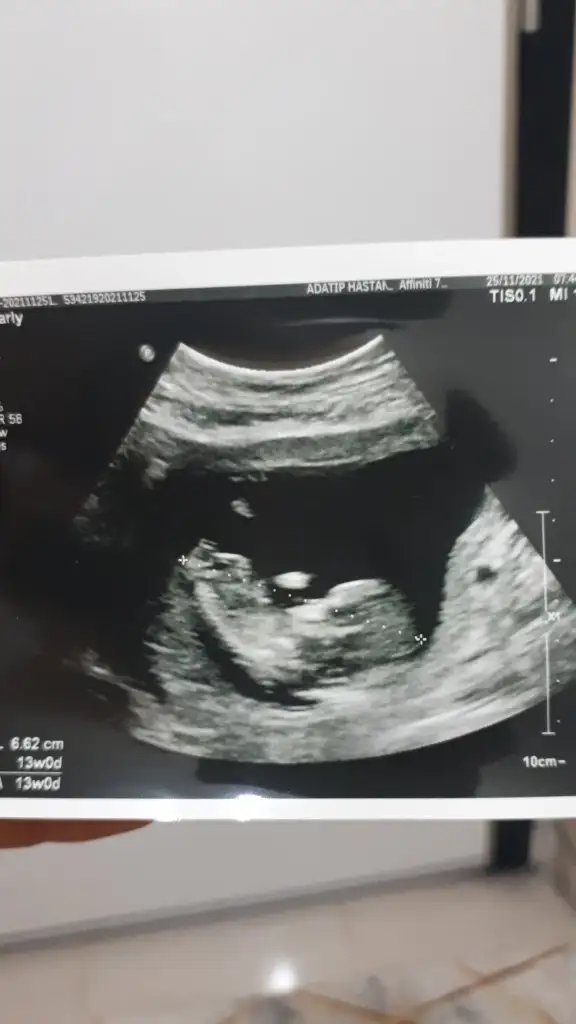

Doktor erkek gibi duruyor dedi ama bakalim net değilEmin olamadım kız gibi sanki

Canım bizde 13 haftalık olduk geldik bakar mısın

Doktor bir şey demedi

Erkek sankiİkra hanım merhaba 12 hafta görüntülerini ekledim sizce nedir cinsiyeti